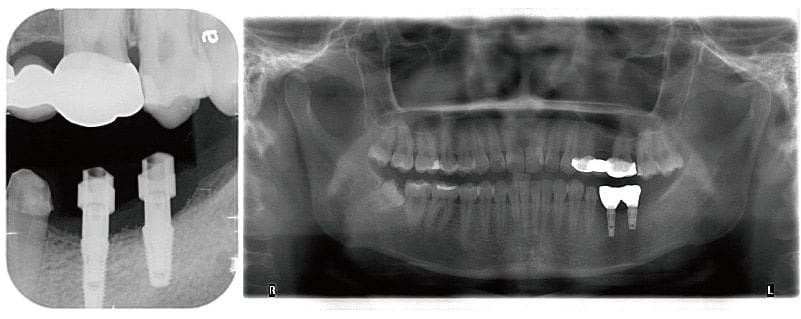

右圖為植體露出換上癒合帽,同時把牙齦補寬,補肉手術增寬牙肉後大約 6-8 週,我們利用數位牙科的技術與特殊植牙的口內掃描套件,就可以有效率且精準地把植牙假牙完成。

圖示:鎖上數位套件掃描後植牙完成的X光片

圖示:完整牙周病治療後,進行植牙手術的前後對比照